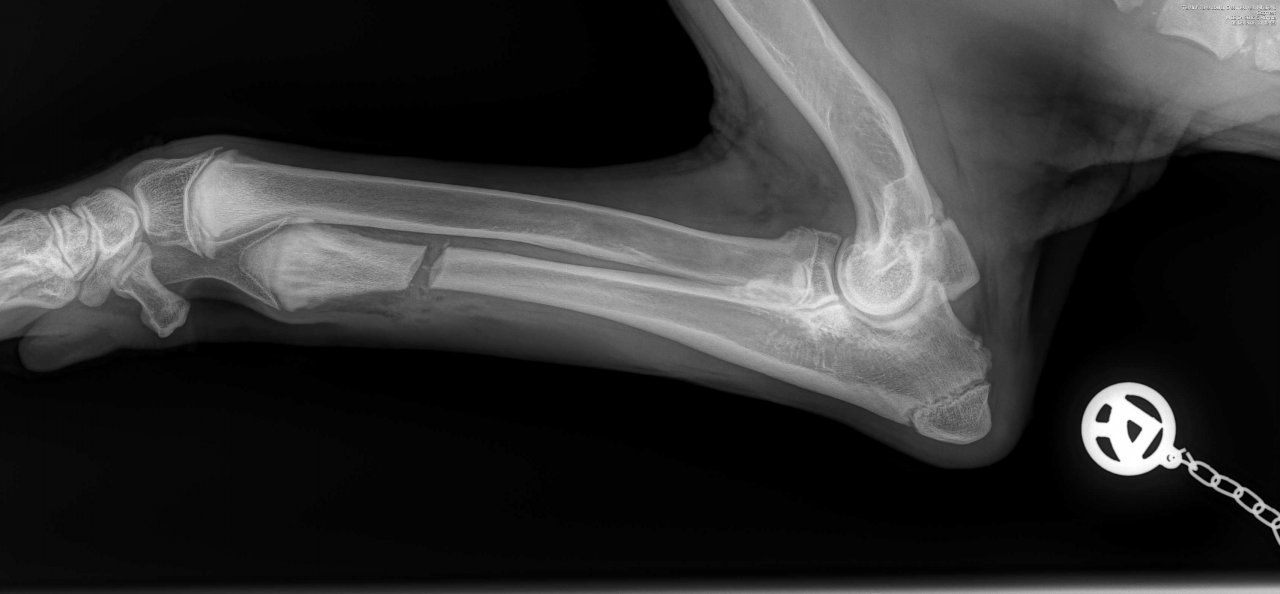

Sooo habe nun auch die Nachher Bilder ich stelle nochmal beide rein also vorher und nachher.

Da sieht man schön den Knochenbruch der Ulnaresektionsosteotomie. Sind aber wohl unterschiedliche Postionen vor und nach der OP der Aufnahmen

Auf dem oberen Bild sieht man deutlich das Fragment auf der rechten Seite das entfernt wurde. Selber am Gelenk hab ich es auch nur mit der Unterstützung vom Arzt gesehen. Also bei den seitlichen Aufnahmen da erkenne ich ohne Anleitung auch nichts. Die ct Aufnahmen checkt man auch nur mit Arzt Erklärung